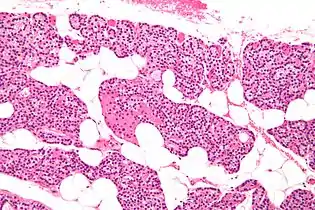

Intermediate magnification micrograph. H&E stain. The white round structures are fat cells. Adipose tissue comprises 25–40% of normal parathyroid gland tissue.[7]

The parathyroid glands are named for their proximity to the thyroid—and serve a completely different role than the thyroid gland. The parathyroid glands are quite easily recognizable from the thyroid as they have densely packed cells, in contrast with the follicular structure of the thyroid.[6] Two unique types of cells are present in the parathyroid gland:

- Chief cells, which synthesize and release parathyroid hormone. These cells are small, and appear dark when loaded with parathyroid hormone, and clear when the hormone has been secreted, or in their resting state.[7]

- Oxyphil cells, which are lighter in appearance and increase in number with age,[7] have an unknown function.[8]